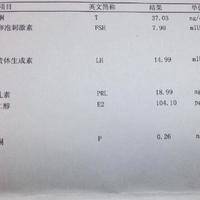

试管移植前雌激素很高的情况下能移植鲜胚吗?

问题描述:今天刚做了取卵手术,过几天就要做移植手术了。按照医生的建议在这之前要去医院做移植前的身体状况检查。从结果来看我雌激素很高,虽然我知道移植对身体状况有严格要求,因此想问问这个情况下能移植鲜胚吗?最佳回答:一般移植鲜胚要求雌二醇水平在6000pg/ml之内。如果在移植前该激素高于正常值的话,很可能会影响到内膜成长、影响到激素平衡继而降低着床成功率。每个试管女性在移植前医生都会要求其做详细身体...

多囊女性打试管促排针后fsh越来越高会影响卵泡发育吗?

问题描述:我在备孕无果后去医院做了生育检查,确定自己患有多囊所以导致自然怀孕很困难。综合多种因素,医生建议我去做试管治疗,但在打了促排针后去检查,发现fsh这一激素值越来越高,我就担心会影响到治疗结果。因此想问问大家这个激素变高的情况下会影响卵泡发育吗?最佳回答:促排期间抽血检查发现fsh越来越高是正常的,因为促排卵药物使用目的就是为了促进卵泡生长发育,而fsh也是促进女性卵泡的生长发育,那么在使...

做完试管移植后两个月fsh特别高是怎么回事?

问题描述:我很早之前检查出有子宫内膜异位症的情况,于是和老公去医院做的试管婴儿,现在已经移植了两个月多了,今天去检查,发现fsh特别高,我想问问这是怎么回事呢?最佳回答:可能是由于卵巢功能下降、药物影响、妊娠状态等的影响,如果试管移植后两个月FSH特别高,建议及时就医,向专业医生咨询并接受进一步检查。医生会根据患者的具体情况制定个性化的治疗方案。在试管移植后两个月出现FSH(促卵泡激素)特别高的情...